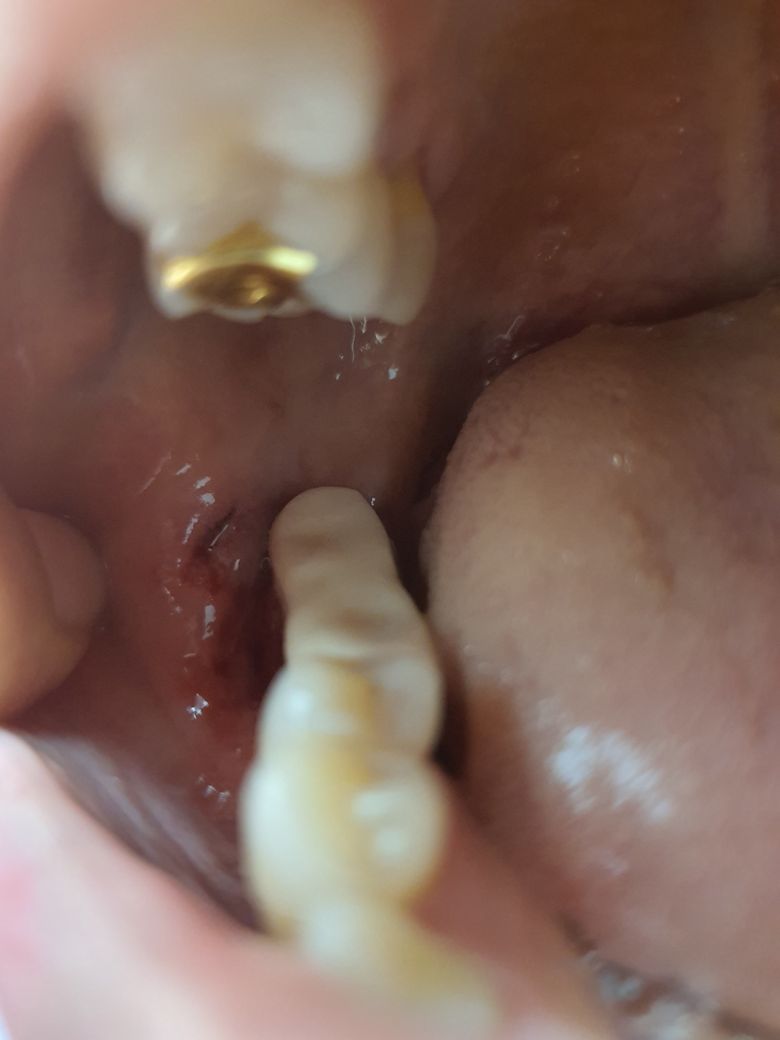

치과치료 도중 볼살이 찢어졌어요 괜찮을까요?

임플란트 기둥을 깎다가 볼 살을 기계로 왔다갔다 찢으셨어요 치과원장님이..

꽤 깊은데 아물어 가긴 하는데 오늘은 갑자기 좀 매운거 먹었더니 시렵더라구요

• 2번 째 사진

특별히 감염증소견이 보이지는 않는 것으로 보아 시간이 지나면 회복될 것 같습니다. 부어오르고 더 아파온다면 치료가 필요하니 병원을 방문하시기 바랍니다.

• 구강내 병변은 출혈만 많지 않으면 걱정하지 않으셔도 됩니다. 왠만하면 잘 아물더라구요...

출혈이 많으면 어쩔 수 없지 꼬매기는 하지만...